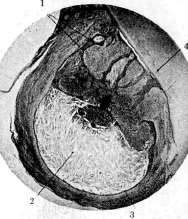

Рисунок 2. Кистовидная гранулема: 1 тяжи эпителия; 2 полость гранулемы, в содержимом которой находится большое количество кристаллов холестерина; 3 эпителиальная выстилка полости; 4 корень зуба.

Рисунок 3. Зубная гранулема in situ (трупный материал): 1 перицемент; 2 костные стенки альвеолы; 3 -фиброзная капсула гранулемы, переходящая в перицемент (вследствие наличия гранулемы и рассасывания костной ткани в области дна альвеолы в периапикальном губчатом костном веществе образовалось лишенное костных балок пространство, выполненное тканью гранулемы); 4 -гранулема; 5- корень зуба.